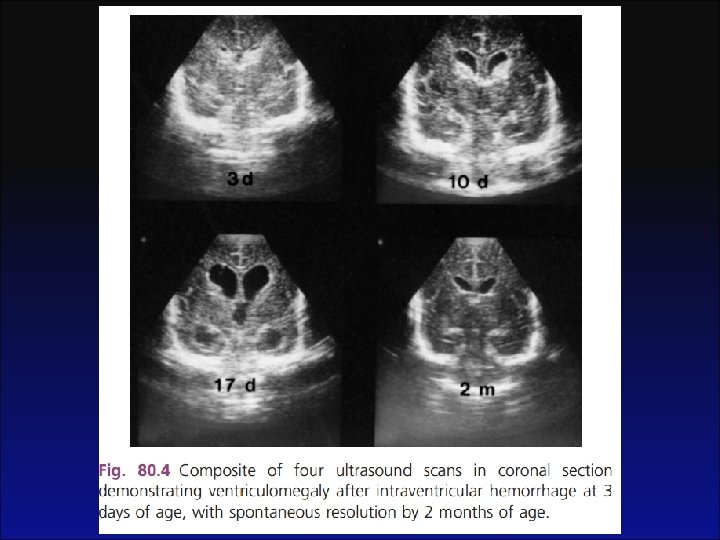

Segmento • LCR + Ultrassom transfontanela (no diagnóstico; 48 horas; 1 semana). • Evolução tranquilizadora em 24 -48 horas de ATB: não é necessário repetir LCR • Evolução desfavorável: repetir com 48 a 72 horas de ATB

Preditores de Prognóstico Adverso • Preditores de prognóstico adverso são: convulsões, coma, uso de inotrópicos e leucopenia. • As anormalidades no US craniano estão presentes por volta de 65% das crianças com meningite bacteriana, chegando, no entanto a 100% com 48 horas de vida nos casos de deterioração tanto clinica como laboratorialmente. Há recomendações de um exame ultrassonográfico inicial ao diagnóstico da meningite e repetir semanalmente se forem detectadas alterações no exame inicial (anormalidades parenquimatosa ou ventricular) ou se o paciente apresentar deterioração clínica (aumento do perímetro cefálico, achados neurológicos, falta de resposta ao tratamento).